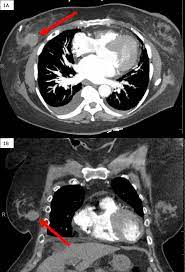

Can A Ct Scan Show Breast Cancer - Cureus Hematoma Mimicking Breast Cancer On Ct Scan And Breast Ultrasound : Doctors can combine pet scans with ct scans.. A pet/ct scan is a newer technology used to create images of the body's cells as they work. However, multidetector computed tomography (ct) often provides the first images of the breast when scanning is performed for pulmonary or cardiac disease. Yes though that is not the test of choice. I went to a breast cancer disucussion given by my local hospital during october. It's an effective imaging test for finding cancer and learning its stage.

However, multidetector computed tomography (ct) often provides the first images of the breast when scanning is performed for pulmonary or cardiac disease. My bone mets were discovered during a bone scan (i.e. It is common for patients to receive a diagnosis for cancer of unknown primary. Breast pet scans are known as positron emission mammography (pem). Ct scan (computerized tomography) of the chest, abdomen, and pelvis;

The term tomography comes from the greek words tomos (a cut, a slice, or a section) and graphein (to write or record). My bone mets were discovered during a bone scan (i.e. This test is most often used to look at the chest and/or belly (abdomen) to see if breast cancer has spread to other organs. Doctors often use ct scans to help them guide a needle to remove a small piece of tissue. Nuclear) and show up on my ct scans as well. When you do a ct scan it is to find the tumors or other suspicious spots in your lungs, adrenal gland, liver, ribs and parts nearby. Bone scans and ct scans are not routine tests for breast cancer and are only done if the cancer has a high risk of spreading. Each picture created during a ct procedure. Pet scans can also help to assess whether metastatic breast cancer is responding to the treatment. Mammography is currently the preferred examination for breast cancer screening; However, your doctor may call this a pet scan. If you have more tests, your risk increases. It is common for patients to receive a diagnosis for cancer of unknown primary.

This helps determine whether or not the cancer can be removed with mastectomy. A chest ct will usually spot breast cancer as an incidental finding. In some instances, cancers may not show on the scan. This can increase your risk of cancer. I went to a breast cancer disucussion given by my local hospital during october.

A chest ct will usually spot breast cancer as an incidental finding. The ct scan might show signs of cancer, but that cancer might not be active for example, it could be scar tissue left over from cancer killed off by your treatment Ct scans can show a tumor's shape, size, and location. This can allow for examination of neighboring organs and structures like lymph nodes to check for any signs of disease. Mammography is currently the preferred examination for breast cancer screening; I was told that a bone scan is often used for diagnosis whereas ct scans can be used for follow up scans. This test is most often used to look at the chest and/or belly (abdomen) to see if breast cancer has spread to other organs. A pelvic ct scan can be used to detect several types of cancer. I went to a breast cancer disucussion given by my local hospital during october. In some cases, physicians use all three imaging techniques. Yes though that is not the test of choice. The combination test can provide a clearer picture of the location, spread, and growth of a tumor than either test by itself. The cancer's stage describes the location of cancer, if it spread and if it's changing the function of your organs.

This can allow for examination of neighboring organs and structures like lymph nodes to check for any signs of disease. After detecting the location of the tumor, the area will be biopsied for testing in the lab. A sentinel lymph node biopsy may first be performed to determine whether cancer has spread to the lymph glands under the arm. If you have a large breast cancer, your doctor may order a ct scan to assess whether or not the cancer has moved into the chest wall. When a breast cancer has been diagnosed, some people have a ct scan of their chest and tummy (abdomen) to stage the breast cancer. A mammogram, ultrasoud or mri (that they now do for breast) are tools to find tumors in the breast is my understanding. During a ct scan, you will be exposed to a small amount of radiation. Ct/pet together in one scan is a more advanced scanning method that is especially helpful in detecting and diagnosing cancer in soft tissues. Ct scan (computerized tomography) of the chest, abdomen, and pelvis; It's an effective imaging test for finding cancer and learning its stage. The equipment can be set to capture a larger area, as well, during a breast ct scan. Knowing the stage helps your doctor decide which treatment you need. These scans use large amounts of radiation.